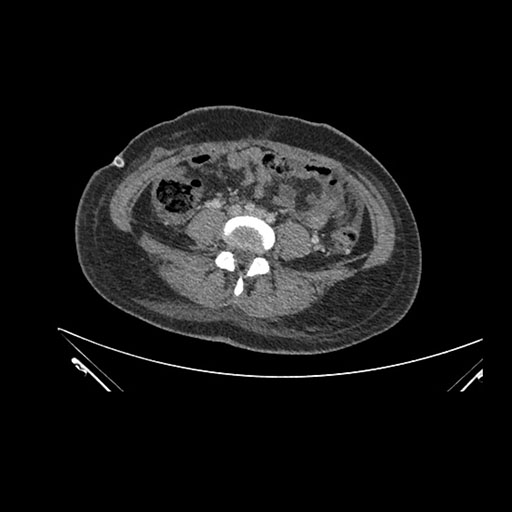

Imaging Analysis

Look through the patient's CT scan to identify any areas of concern for the necessary procedure.

Axial Arterial

Axial Venous

Based on initial findings, which issue(s) would you be most concerned about?